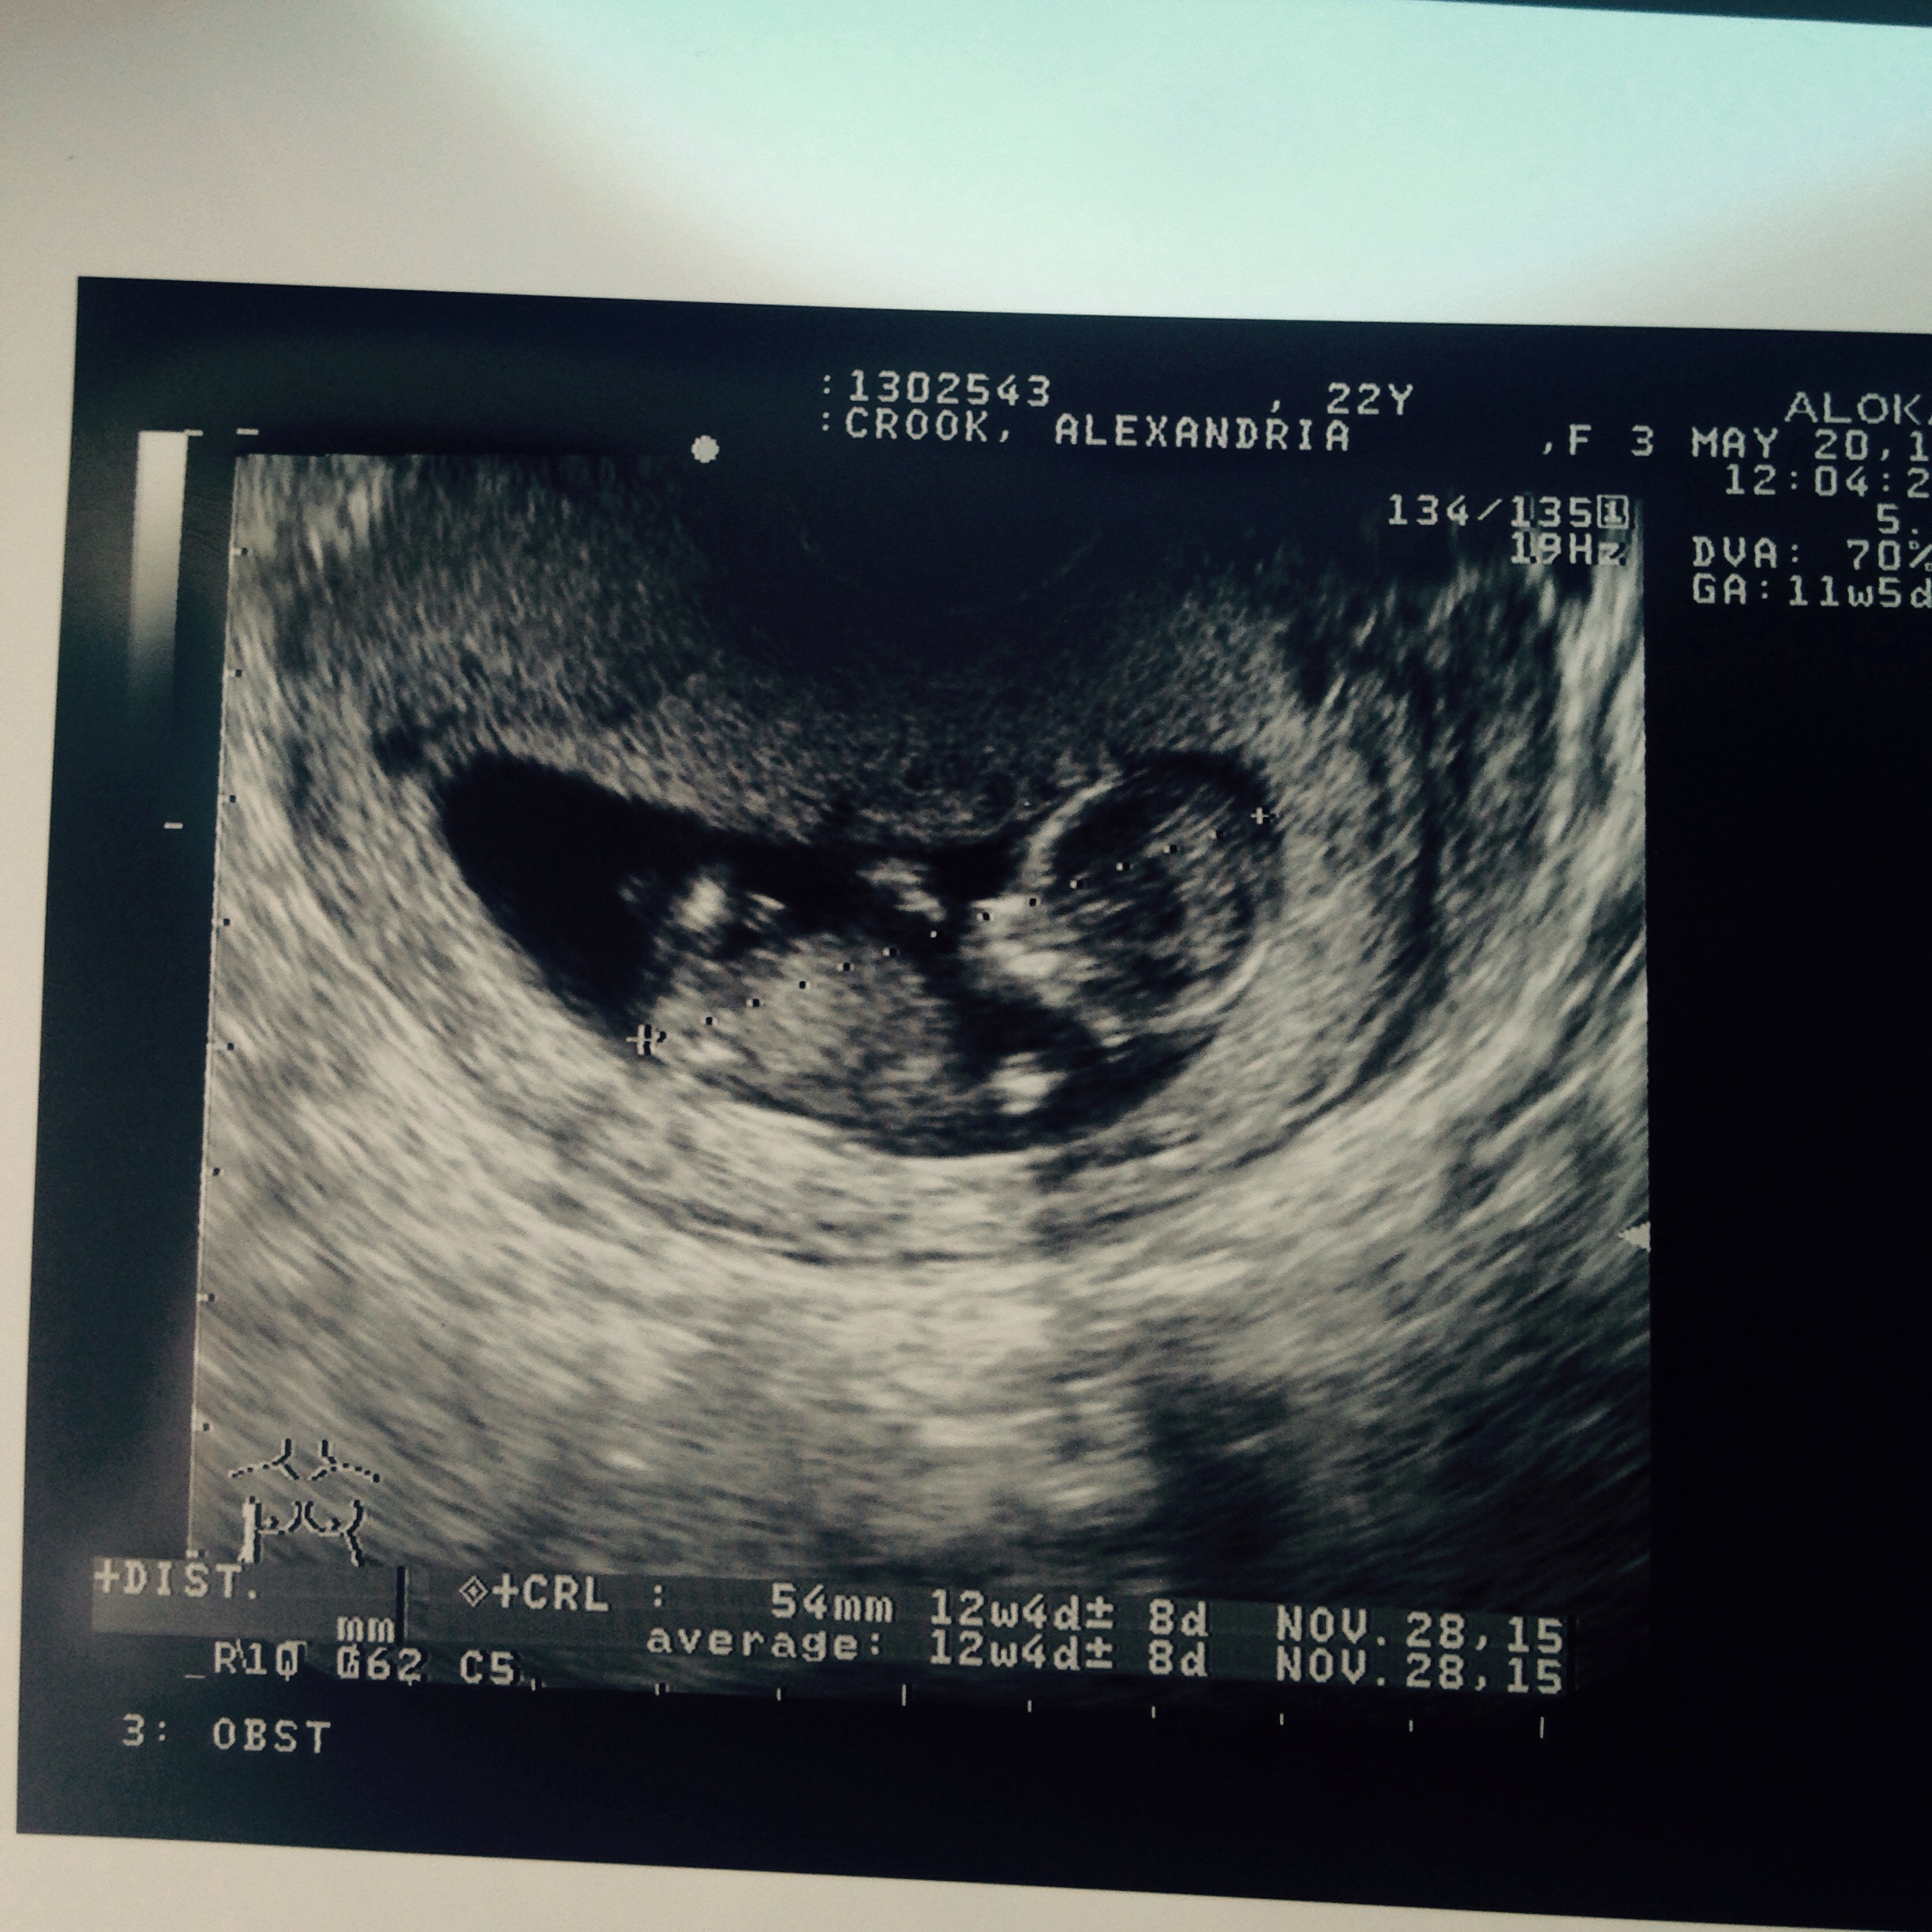

My baby at 11 weeks! Can't wait to have my 12 week scan on Tuesday